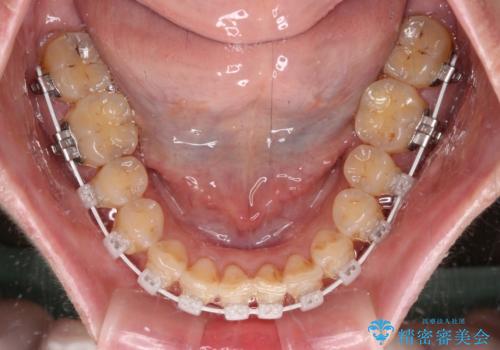

- 審美装置

なるべく早めに治療を終えたいとのことで、補助装置を用いて上顎臼歯を後方に移動させ、同時にワイヤー装置にて整えることとしました。

舌の突出癖が原因で上下の歯に大きなスペースが生じていたため、舌のトレーニングをしっかり行っていただくことで、上顎歯列をスムーズに移動させることができました。